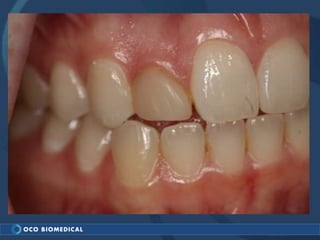

A 3.0mm dental implant was placed to replace congenitally missing maxillary lateral incisors. Dr. Tim Kosinski used a 1.8mm pilot bur and tissue punch to prepare the osteotomy site, then placed the implant by hand and seated it with a torque wrench. After ensuring the implant trajectory was within the restorative envelope, an acrylic coping was placed for temporary fabrication. At the 1 week post-op appointment, excellent soft tissue response and papilla formation were observed, and a final impression was taken to send to the lab for crown fabrication.